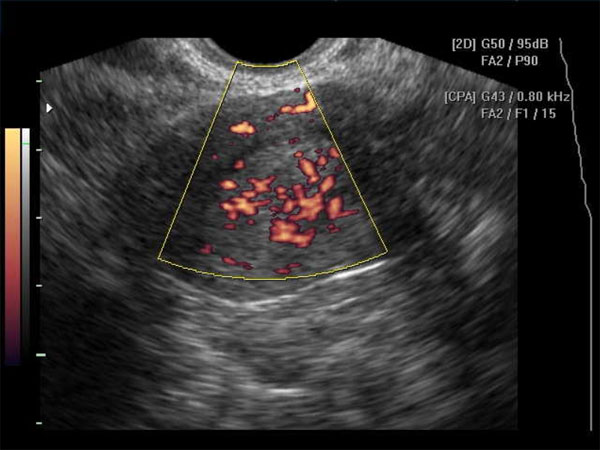

Когда дело доходит до визуализации, этим пациентам обычно назначают трансвагинальное ультразвуковое исследование, чтобы определить, есть ли причина боли в области таза, которую можно визуализировать.Поверхностные имплантаты эндометриоза нельзя увидеть ни на УЗИ, ни на каком-либо другом методе визуализации. Однако эндометриомы часто обнаруживают на УЗИ. Эндометриомы обычно выглядят как простые кисты. Однако их также можно рассматривать как множественные кисты или кистозно-солидные образования. Типичный вид этих поражений на УЗИ демонстрирует низкоуровневые однородные эхо-сигналы, иначе описываемые как внешний вид матового стекла. Это согласуется со старым геморрагическим мусором. Эти поражения также обычно лишены какой-либо васкулярности при исследовании с использованием допплеровского потока.[35] [36]

Если опухоль придатков присутствует и известна из изображений, есть характеристики массы, которые могут указать, что это за образование придатков.Эндометриомы, как обсуждалось в разделе оценки выше, имеют характерный вид матового стекла на УЗИ. Эти результаты также наблюдаются при геморрагических кистах, и часто диагноз между ними не устанавливается до момента операции. Поэтому, имея дело с визуализацией эндометриом, важно учитывать геморрагические кисты при дифференциальном диагнозе. [52]